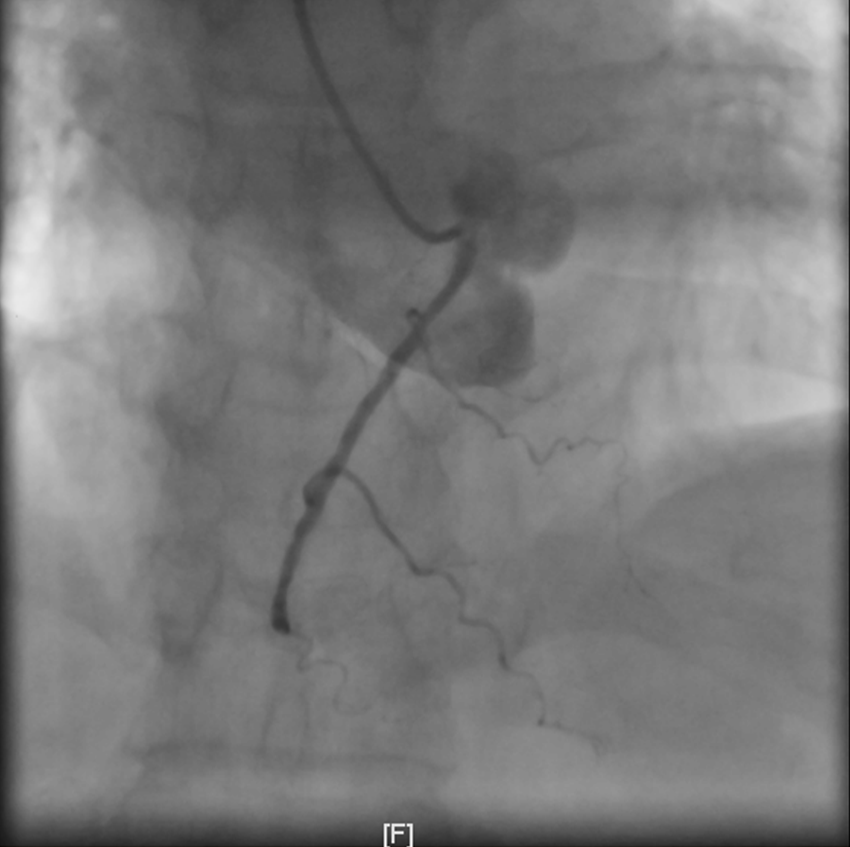

血管堵塞

与余女士家属积极沟通后,余女士家属签署知情同意书,同时余女士在做好防护措施后立即送入介入室。在覃主任的带领下,陈志明副主任医师手术团队凭着娴熟的技术,仅用了33min开通患者罪犯血管—右冠中段闭塞血管,成功挽救了余女士的生命。术后余女士送入心血管内科CCU继续治疗,目前已康复出院。